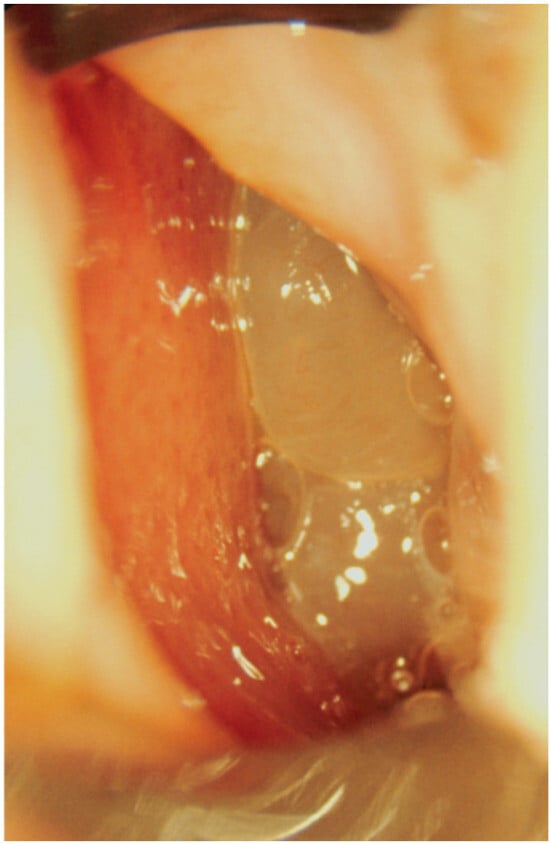

- 0 = no polyps;

- 1 = polyps confined to the middle meatus;

- 2 = multiple polyps occupying the middle meatus;

- 3 = polyps extending beyond the middle meatus;

- 4 = polyps completely obstructing the nasal cavity.

- 1 = small polyps in the middle meatus not reaching the inferior border of the middle meatus;

- 2 = nasal polyps reaching below the lower border of the middle meatus;

- 3 = large polyps reaching the lower border of the inferior turbinate or polyps medial to the middle turbinate;

- 4 = large nasal polyps causing complete obstruction of the inferior nasal cavity.

- Djupesland, P.; Reitsma, S.; Hopkins, C.; Sedaghat, A.; Peters, A.; Fokkens, W.J. Endoscopic grading systems for nasal polyps: Are we comparing apples to oranges? Rhinology 2022, 60, 169–176. [Google Scholar] [CrossRef] [PubMed]

- Gevaert, P.; Gevaert, P.; De Craemer, J.; De Craemer, J.; Bachert, C.; Bachert, C.; Blauwblomme, M.; Blauwblomme, M.; Chaker, A.; Chaker, A.; et al. European Academy of Allergy and Clinical Immunology position paper on endoscopic scoring of nasal polyposis. Allergy 2023, 78, 912–922. [Google Scholar] [CrossRef] [PubMed]